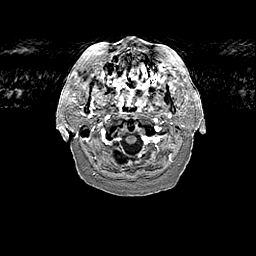

Glioma overlay -- Slice #4

[Home][Help][Clinical] Slice 4